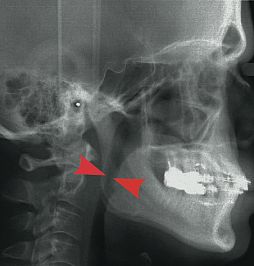

However, some individuals seek a solution for OSA which will allow them freedom from nightly CPAP or oral appliances. Dr. Bates provides surgical procedures for treatment of OSA, depending on the location of the obstruction and the severity of the apnea. Studies have shown that maxillomandibular advancement, or MMA, has the highest success rate in the treatment of severe OSA. MMA involves performing orthognathic (or “telegnathic”) surgery to make a series of cuts, or osteotomies, in the upper and lower jaws, allowing them to be separated and significantly advanced, or moved forward. Because the soft tissues in the airway which cause the obstruction, the soft palate and the tongue, are attached to the jaws, this results in a significant increase in posterior airway space which can be noticed dramatically in the before and after x-rays seen below.